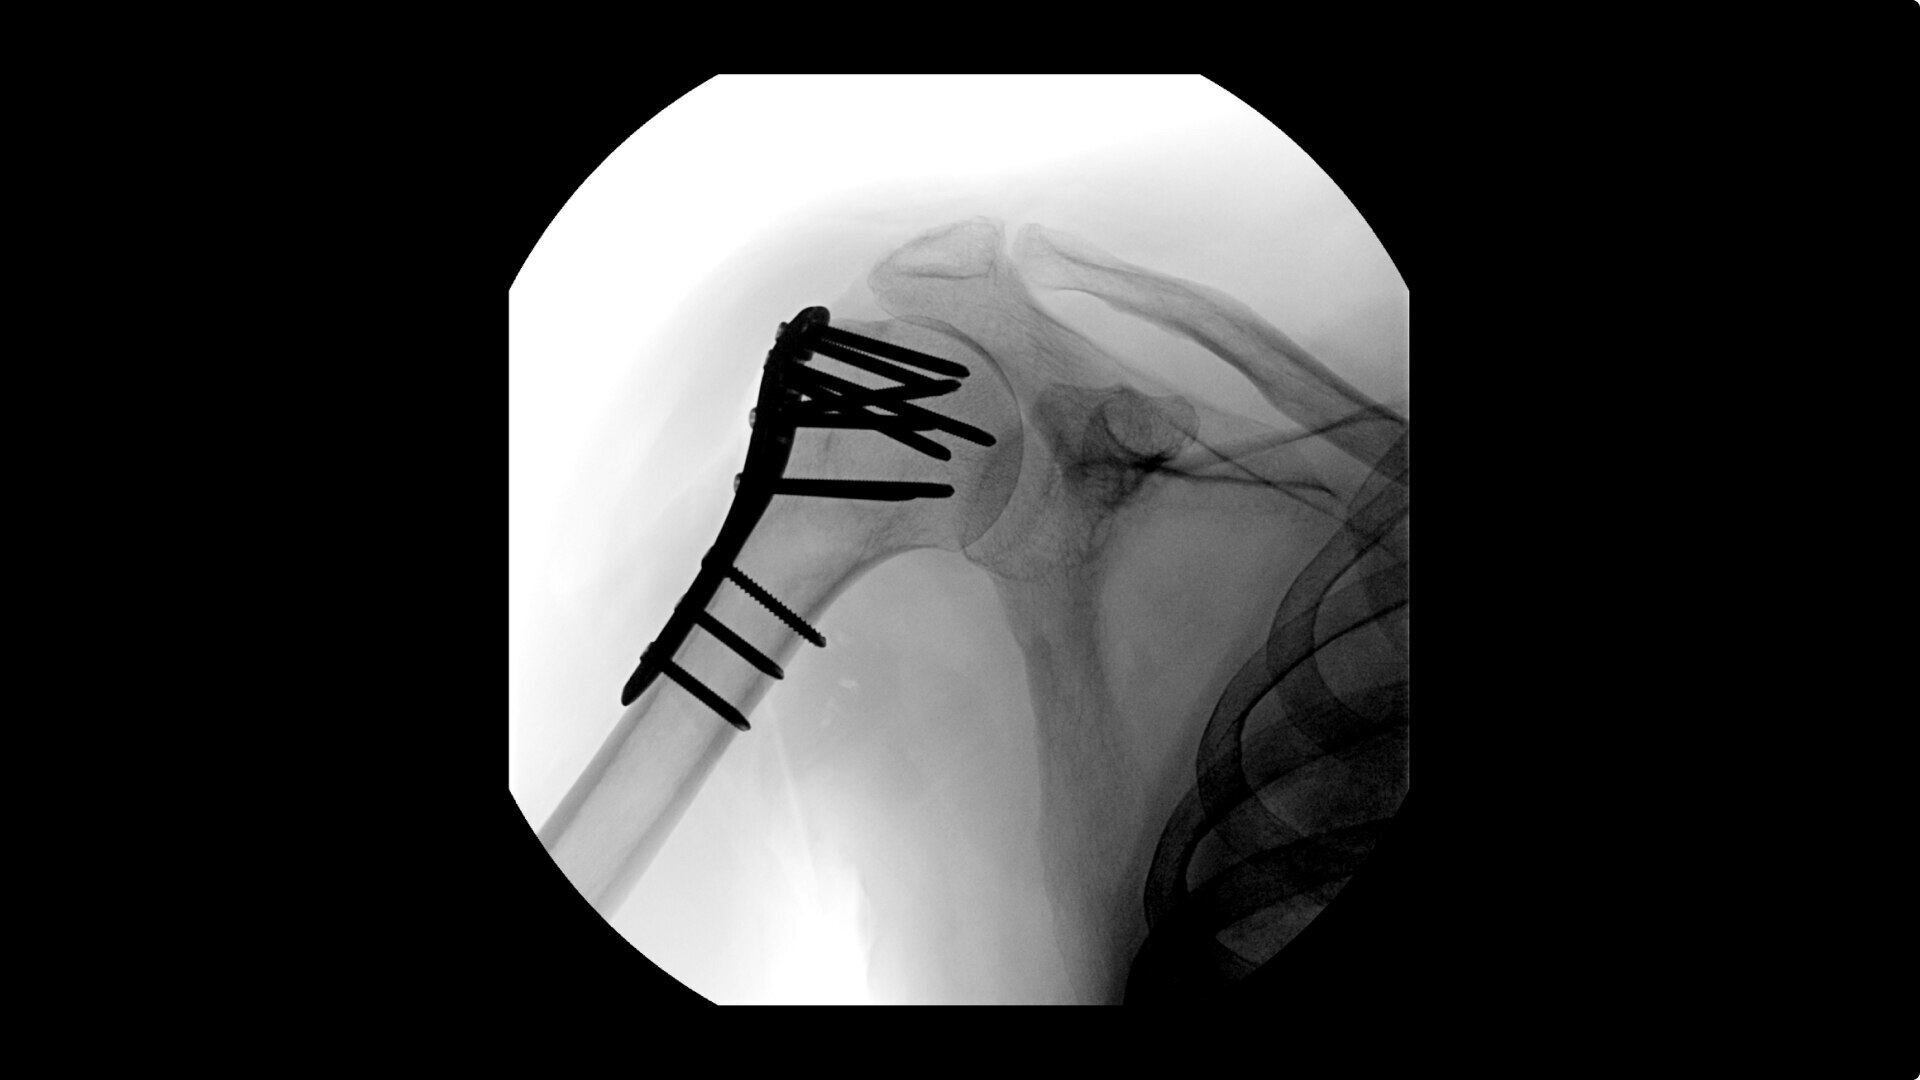

Live Zoom up to 4X during a fluoro without the additional dose of Mag modes to assess orthopedic fractures and fixations.

See precise anatomical detail of varying densities such as bone and soft tissue with a high dynamic range with the OEC Elite CFD with a flat detector, image processing advancements and 4K viewing display.

Complex orthopedic procedures require powerful imaging systems. OEC premium C-arms perform in a variety of procedures such as: